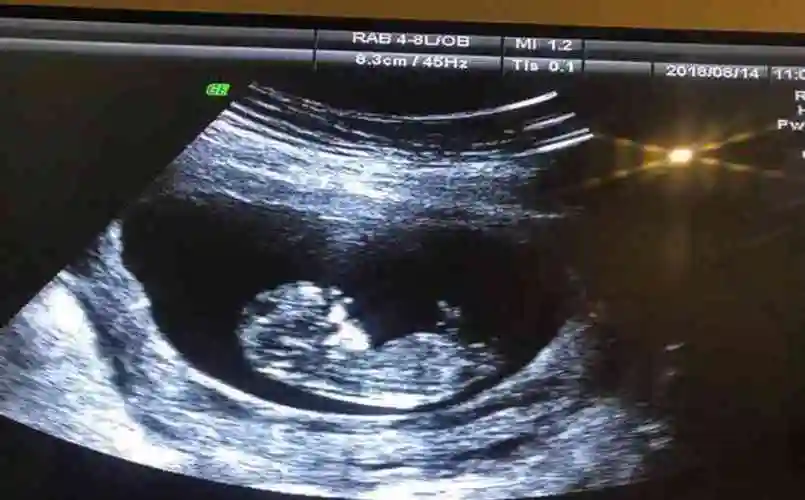

孕12周nt检查显示有三个亮点是男孩还是女孩

这个是三条线吗是不是女宝

求问我这三条线是肯定女宝了吗?

2,四维3个亮点是男孩:怎样可以看出四维彩超上是男孩还是女孩